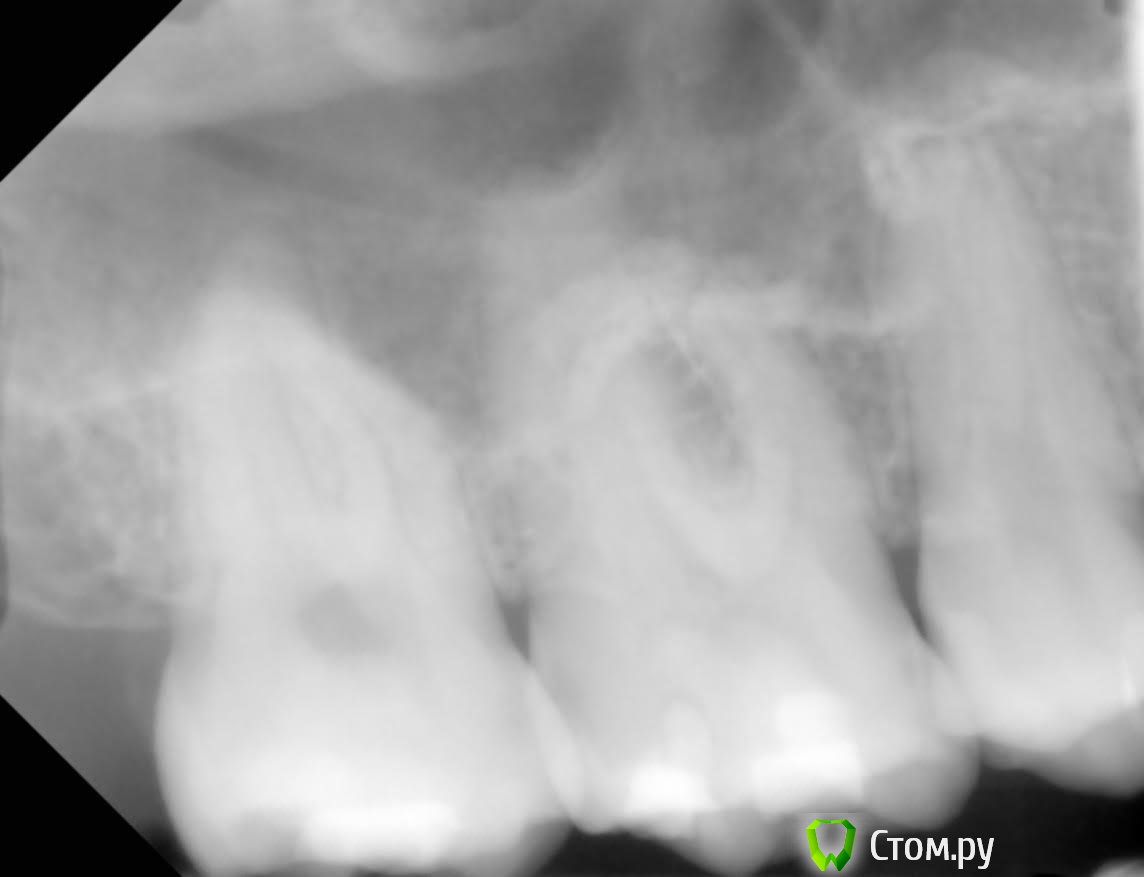

Юлия Арт Опубликовано 12 марта, 2014 Поделиться Опубликовано 12 марта, 2014 здравствуйте! мне всего 26 лет, ситуация с зубами у меня критическая, уже 2 удалены из-за больших кист под ними, сейчас болят сильно три коренных зуба наверху 8-6-4 , болели обычно когда ела, старалась избегать контакта с ними, языком пробовала зубы-стреляло сильно. Врач посмотрел снимки, сказал что пломбы очень глубокие, доходят до нервов, выход только удалять нервы. Пару дней назад начали удаление нервов в 3-х зубах, боль пульсирующая прошла, на холодное не болит, но докасаться до зубов невозможно, болит так же! есть на них не могу, если по зубам постучать-небольно,но если немного из стороны в сторону надавить на некоторые участки этих зубов - болит сильно! Уже не знаю что делать...врач говорит что надо подождать, но чего ждать когда мне ясно что удаление нервов не помогло. Уже думаю, может, они поломаны...есть снимок до удаления нервов пожалуйста, помогите советом что делать и что может быть с моими зубами Ссылка на комментарий

Юлия Арт Опубликовано 12 марта, 2014 Автор Поделиться Опубликовано 12 марта, 2014 снимок сделан в прошлом году, другого пока нет. нижняя 6-как и верхняя 5-ка удалены так как кисты под ними были.3 зуба с нервами за 2 дня депульпировали так как болело так что обезболивающее не брало... уже сомневаюсь что надо было это делать, хотя каналы кровили во всех зубах-пульпит был долгое время Ссылка на комментарий

Юлия Арт Опубликовано 13 марта, 2014 Автор Поделиться Опубликовано 13 марта, 2014 вот фото, панорамный сделали сегодня (вторая кист куда-то делась у верхней 5-ки, вырывать зуб не стали),троица с депульпцией болит и ноет сильно, есть на них не могу Ссылка на комментарий

anvladd Опубликовано 13 марта, 2014 Поделиться Опубликовано 13 марта, 2014 17 зуб похоже проблемный уж слишком пломба глубоко. Ссылка на комментарий

Л Ю С Я Опубликовано 13 марта, 2014 Поделиться Опубликовано 13 марта, 2014 1.4 перелечивать, разобраться с 1.7 и 1.5, возможно и 1.6 проблемный Ссылка на комментарий

anvladd Опубликовано 13 марта, 2014 Поделиться Опубликовано 13 марта, 2014 Нерв удалили в 16 а вот 17 судя по снимку под подозрением. И как писала доктор выше 14 перелечивать каналы. Ссылка на комментарий

Юлия Арт Опубликовано 13 марта, 2014 Автор Поделиться Опубликовано 13 марта, 2014 (изменено) уважаемые, уже третий день после начала депульпации 7, 6(завершено) и 4-го верхних болит вся цека и все зубы 7-6-5-4...есть на них не могу, такое ощущение что их распирает изнутри, если стучать по ним-небольно, но есть неокторые места куда если пища попадает или пальцем надавить - стреляет больно! через 2 недели только приём у врача на завершение депульпации... а я ждать не смогу, отнимается левая верхняя сторона. судя по фото, что там может быть? или нервы в зубах или , может, они поломаны или десна воспалены? воможности КТ сделать пока нет Изменено 13 марта, 2014 пользователем Юлия Арт Ссылка на комментарий

anvladd Опубликовано 13 марта, 2014 Поделиться Опубликовано 13 марта, 2014 уважаемые, уже третий день после начала депульпации 7, 6(завершено) и 4-го верхних болит вся цека и все зубы 7-6-5-4...есть на них не могу, такое ощущение что их распирает изнутри, если стучать по ним-небольно, но есть неокторые места куда если пища попадает или пальцем надавить - стреляет больно! через 2 недели только приём у врача на завершение депульпации... а я ждать не смогу, отнимается левая верхняя сторона. судя по фото, что там может быть? или нервы в зубах или , может, они поломаны или десна воспалены? воможности КТ сделать пока неттак потому и болит что,как я понимаю,не завершена депульпация 7 и 4 зубов. Вы вложили снимок до или после депульпации, напишите. 1 Ссылка на комментарий

Юлия Арт Опубликовано 14 марта, 2014 Автор Поделиться Опубликовано 14 марта, 2014 так потому и болит что,как я понимаю,не завершена депульпация 7 и 4 зубов. Вы вложили снимок до или после депульпации, напишите.всё верно понимаете, у 6-го каналы вроде почистили, хотя я тут начиталась что их там 4-ре, врач нашёл только 3. 6-й тоже болит сильно, они вообще все с 7-го по 4-й дружно ноют и стреляют. скорее всего там не просто пульпит был, но и периодонтит судя по моим симптомам Ссылка на комментарий

anvladd Опубликовано 14 марта, 2014 Поделиться Опубликовано 14 марта, 2014 тогда долечивать 7,4 и перелечивать 6,искать 4й канал. удачи. Ссылка на комментарий